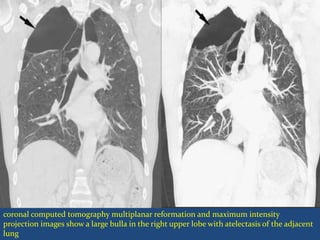

coronal computed tomography multiplanar reformation and maximum intensity

projection images show a large bulla in the right upper lobe with atelectasis of the adjacent

lung

 A giant bulla A bulla that takes up a third or more of

the space in and around the affected lung is called a

giant bulla.

D/D- Loculated Pneumothorax

CT may be necessary to demonstrate the wall of the

bulla or thin strands of lung tissue crossing it.

 Large bullae can compress adjacent more compliant

lung, producing atelectatic pseudomasses

 Predispose to pneumothorax and can reach a very

large size.

coronal computed tomographymultiplanar reformation and maximum intensity projection images show a large bulla in the right upper lobe with atelectasis of the adjacent lung

• 74.

 A giantbulla A bulla that takes up a third or more of the space in and around the affected lung is called a giant bulla. D/D- Loculated Pneumothorax CT may be necessary to demonstrate the wall of the bulla or thin strands of lung tissue crossing it.

• 75.

 Large bullaecan compress adjacent more compliant lung, producing atelectatic pseudomasses  Predispose to pneumothorax and can reach a very large size.